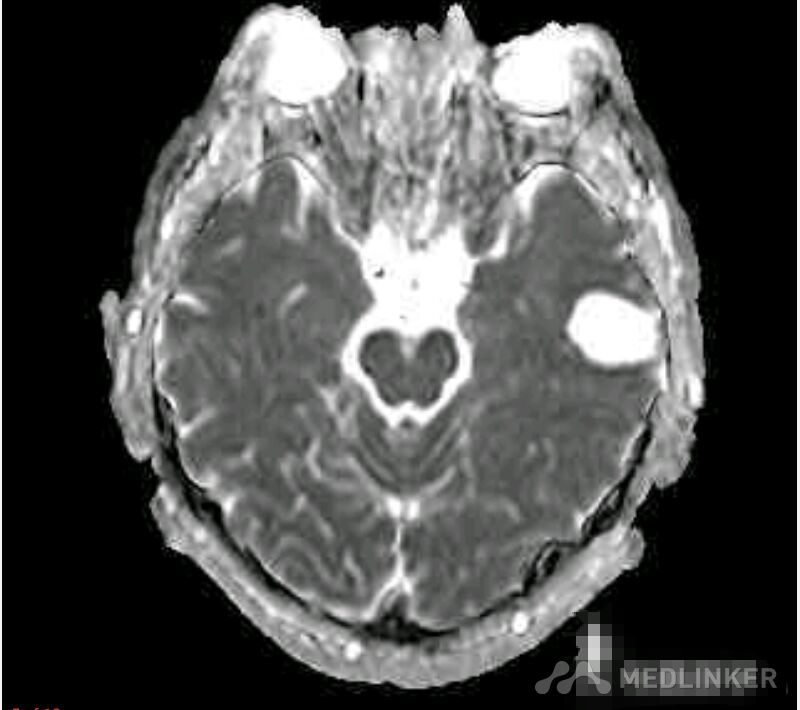

脑囊虫病高清影像资料分享

脑囊虫病经典资料